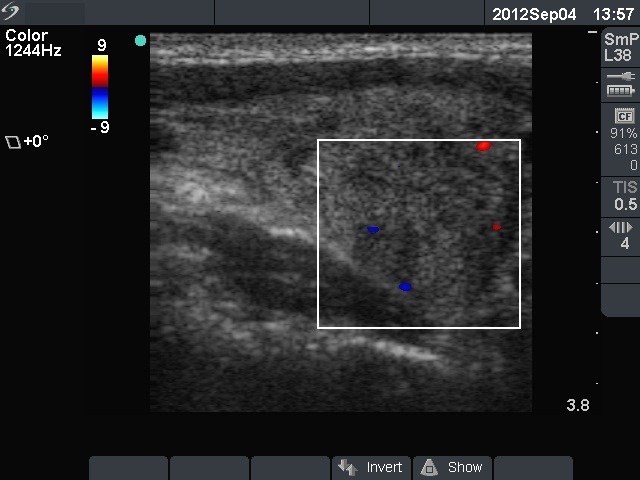

First examination (1st and 2nd rows of images):

Ultrasonography: there were multiple hypoechogenic areas with blurred borders within echonormal background in the left thyroid. The vascularization was decreased. The right thyroid was intact and had normal vascularization.